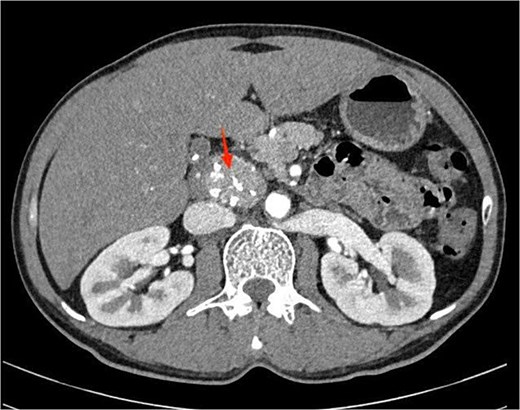

Laboratory investigations were within normal limits. Abdominal ultrasound was unremarkable. A contrast-enhanced computed tomography (CT) scan of the abdomen revealed a well-circumscribed, homogeneously enhancing, hypervascular soft tissue mass, located in the retroperitoneum, anterior to the aorta and posterior to the pancreatic head (Fig. 1). The mass contained punctate calcifications and there was no evidence of enlarged lymph nodes.

Contrast-enhanced abdominal computed tomography showing a well-defined, homogeneously enhancing retroperitoneal mass with punctate calcifications, located anterior to the aorta and posterior to the pancreatic head.